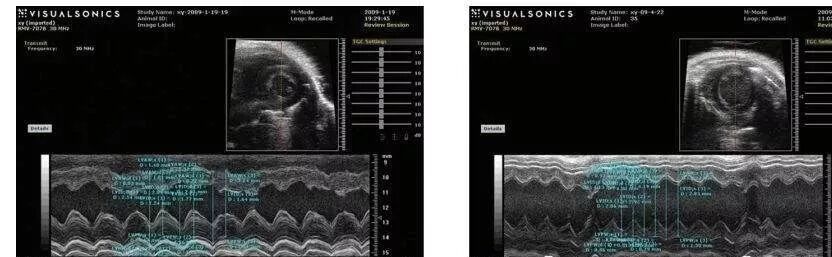

超声心动图显示对照组左室舒张期容积低于移植组